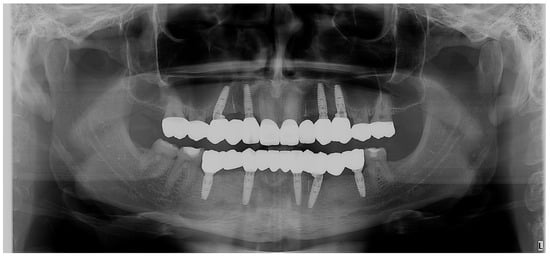

Figure 4.

OPG. Radiographic initial situation of the patient. The radiograph reveals the presence of 7 permanent teeth on the dental arches.

Radiographic examination did not reveal periapical alteration of the present teeth and excluded the diagnosis of dental impaction (Figure 4).